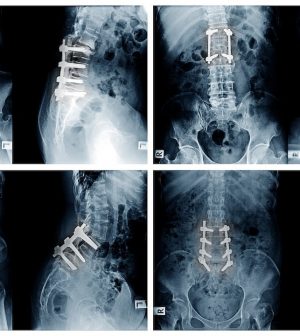

Spinal Fusion Procedures Should Differ Based On Patient’s Sex, Experts Argue

The placement of orthopedic screws and rods during spinal fusion surgery should vary depending on whether you’re a man or a woman, according to a new study.

Sex-based anatomical differences in the pelvis make it essential that surgeons approach men and women differently when fusing and stabilizing the spine, researchers recently wrote in the journal Spine Deformity.

Men have a narrower pelvis, which means that screws and rods need to be placed differently for them than in women.

Specifically, it’s harder to connect screws to rods in a straight line in men, leading to additional rod bending or other adjustments during surgery, researchers said.

Surgery for low back pain sometimes requires that the lower spine be fused, with rods and screws attaching the vertebrae of the lower spine to the pelvis, according to the University of Maryland Medical Center.

For the study, researchers compared 185 cases performed by three orthopedic surgeons, using X-rays and CT scans to assess screw placement and anatomical differences between male and female patients.

Results showed that the narrower pelvis in men causes rods to angle inward, rather than the parallel alignment that’s preferred.